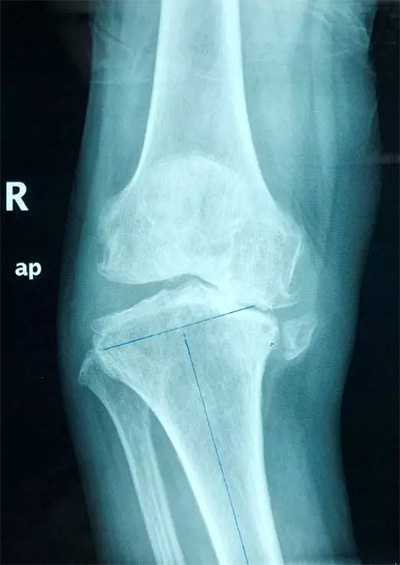

2、全膝關(guān)節(jié)置換

對(duì)于膝關(guān)節(jié)骨性關(guān)節(jié)炎終末期、類風(fēng)濕性關(guān)節(jié)炎、膝關(guān)節(jié)良性或惡性腫瘤的患者,如果膝關(guān)節(jié)疼痛、畸形,經(jīng)過(guò)保守治療無(wú)效,明顯影響生活質(zhì)量,則可行全膝關(guān)節(jié)置換手術(shù)。該手術(shù)可稱為膝關(guān)節(jié)置換術(shù)中的“補(bǔ)牙”技術(shù),應(yīng)用現(xiàn)代材料替代膝關(guān)節(jié)股骨、脛骨關(guān)節(jié)損壞的軟骨表面,從而減輕關(guān)節(jié)疼痛,恢復(fù)關(guān)節(jié)功能。